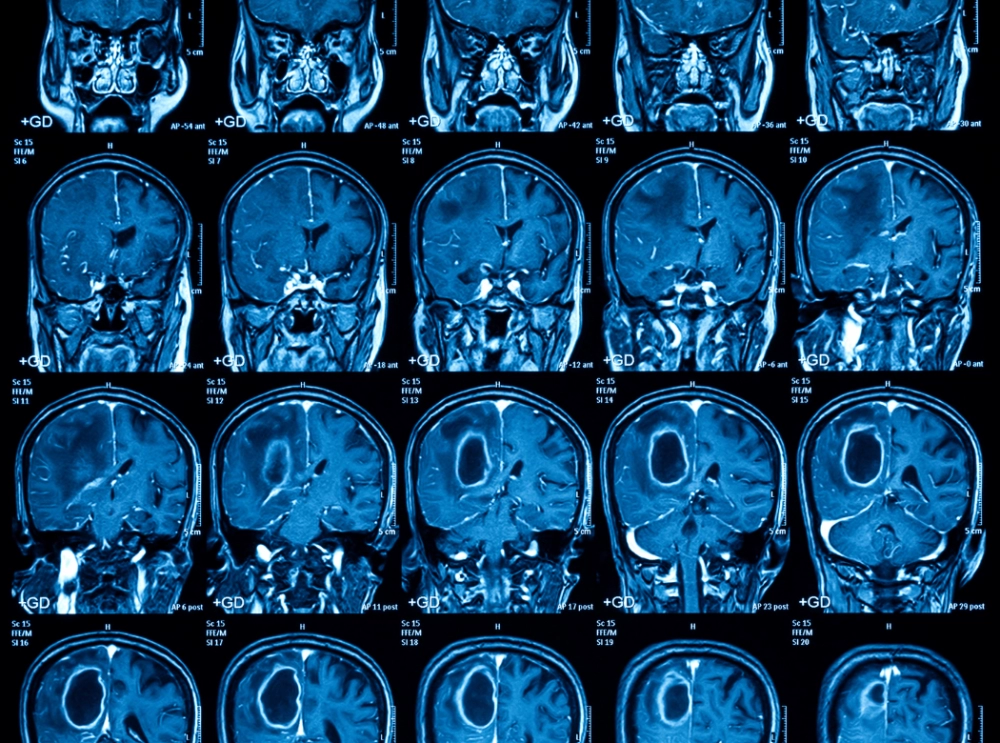

Neurologia

Neurolodzy: Polska nie jest gotowa zmierzyć się z wyzwaniem, jakim są choroby mózgu

Choroby mózgu i układu nerwowego – od udarów, przez padaczkę aż po otępienia i migreny – dotykają milionów Polaków i są jedną z głównych przyczyn niepełnosprawności oraz zgonów – przypominają neurolodzy z okazji Światowego Dzień Mózgu, obchodzonego 22 lipca. Polska nie jest przygotowana na to wyzwanie - zaznaczają.